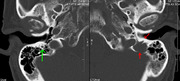

Medical imaging

The diagnostic examination of a person with suspected multiple myeloma typically includes a skeletal survey. This is a series of X-rays of the skull, axial skeleton, and proximal long bones. Myeloma activity sometimes appears as "lytic lesions" (with local disappearance of normal bone due to resorption). And on the skull X-ray as "punched-out lesions" (pepper-pot skull). Lesions may also be sclerotic, which is seen as radiodense.[52] Overall, the radiodensity of myeloma is between −30 and 120 Hounsfield units (HU).[53] Magnetic resonance imaging is more sensitive than simple X-rays in the detection of lytic lesions, and may supersede a skeletal survey, especially when vertebral disease is suspected. Occasionally, a CT scan is performed to measure the size of soft-tissue plasmacytomas. Bone scans are typically not of any additional value in the workup of people with myeloma (no new bone formation; lytic lesions not well visualized on bone scan).